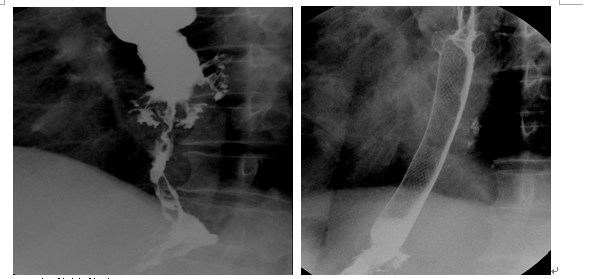

微创介入结合中医药联合支架治疗晚期食道癌

食道癌是我国最常见的恶性肿瘤之一,晚期食道癌患者因不能进食,最终死于衰竭,食道支架置入术可立即解决患者进食困难,术后 同时通过中医察其虚实,根据不同症候分别用理气降逆、燥湿化痰;理气化痰,活血散瘀;清热解毒,养阴生津;健脾益气、化痰祛瘀治疗,可明显提高患者生存期及生活质量。

典型病例:

男、84岁、2012年11月在我院食道造影显示晚期食道癌致纵隔漏,患者反复感染,体质差,行食道覆膜支架一月后复查患者感染消除,身体恢复良好。